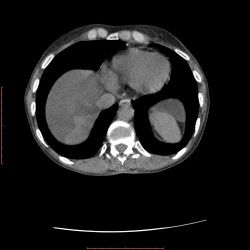

23.05.2014 - 18:08

Мужчина 35 лет, поступил в ХО, желтуха, анемия, субфебрильная t, слабость. УЗИ предположила аневризму аорты. Артериальная фаза Венозная фаза Паренхиматозная фаза...